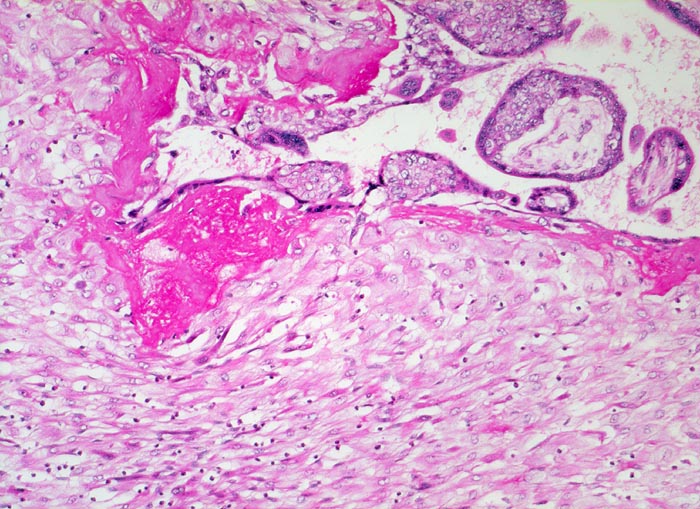

Gravidität: Haftzotten

Normalbefund

Plazenta

Unten im Bild die hellen zytoplasmareichen Deziduazellen mit vesikulären Kernen.

Fibrinoidschicht an der Deziduaoberfläche.

Kernknospe.

11. Schwangerschaftswoche. Normale Schwangerschaft

Histologie

100